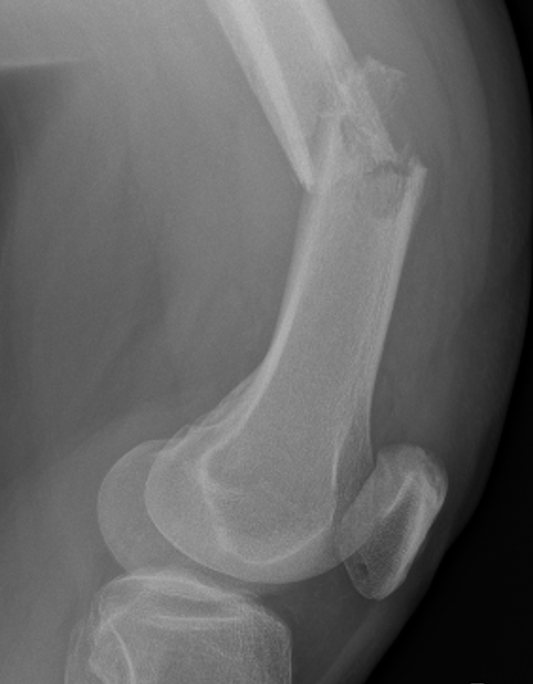

Proximal Humerus

Options

ORIF with plate +/- cement

IMN +/- cement

Tumour prosthesis

Results

Wu et al J Orthop Traumatol 2023

- 45 patients with proximal humerus metastasis

- IM nailing + cement versus plate

- lower blood loss and shorted hospital stay with IMN

- better pain relief with IMN